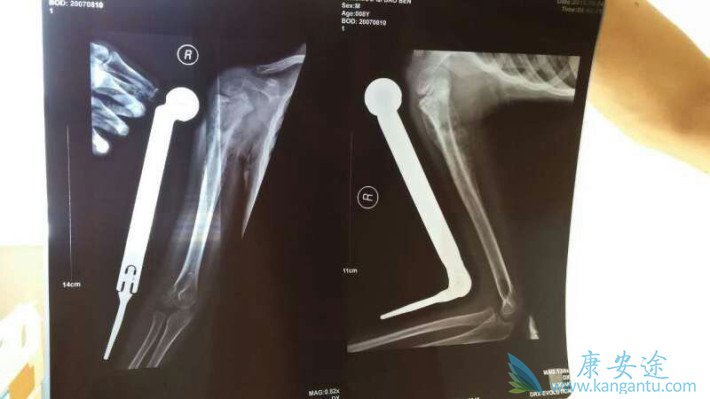

“大约过了20天,打电话的时候女儿说膝盖起了一个鸡蛋大小的包,我开始意识到不对劲,就把孩子接到呼市。”段瑞清说,去医院查了后说是患上骨肉瘤,就是骨癌。

躺在床上的王娜,膝盖肿得和她的大腿一样粗,腿已无法弯曲。一家三口查看着从7月17日入院以来的治疗清单,计算着这段时间的治病费用,“已经花了23000元了。”王宝亮叹了一口气说。